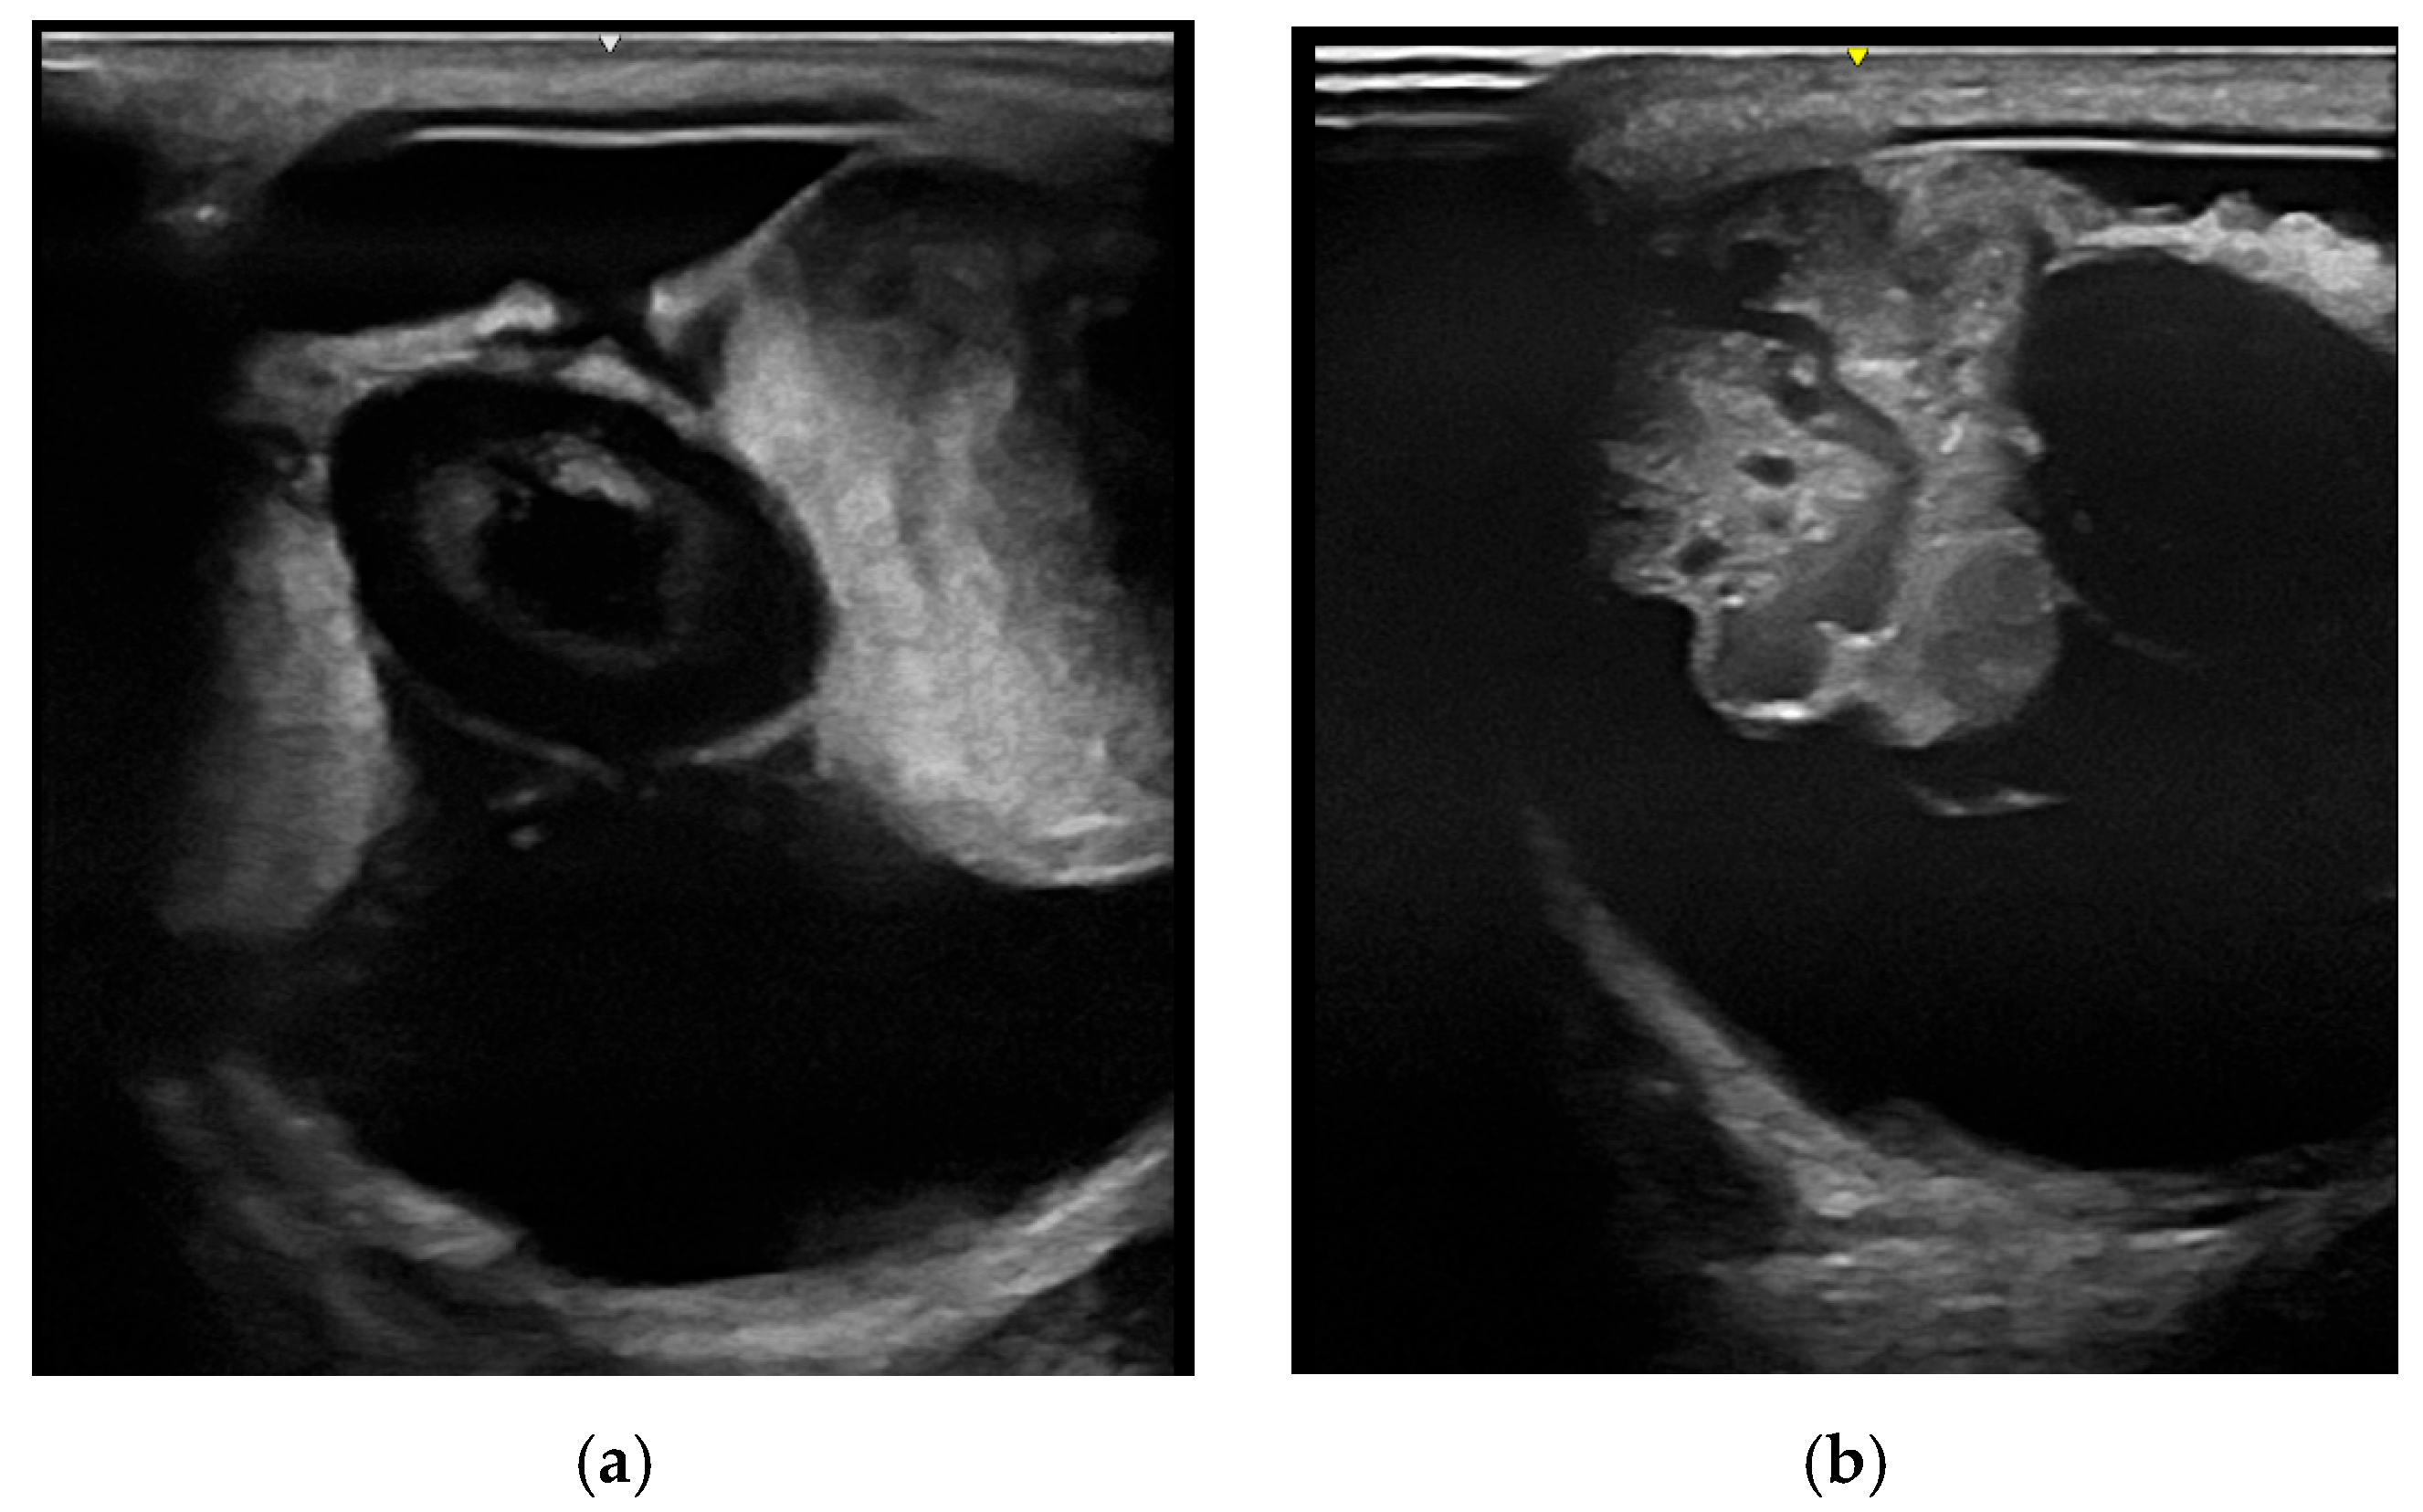

3.2.1. Ultrasonography

3.2.2. Sectional Imaging